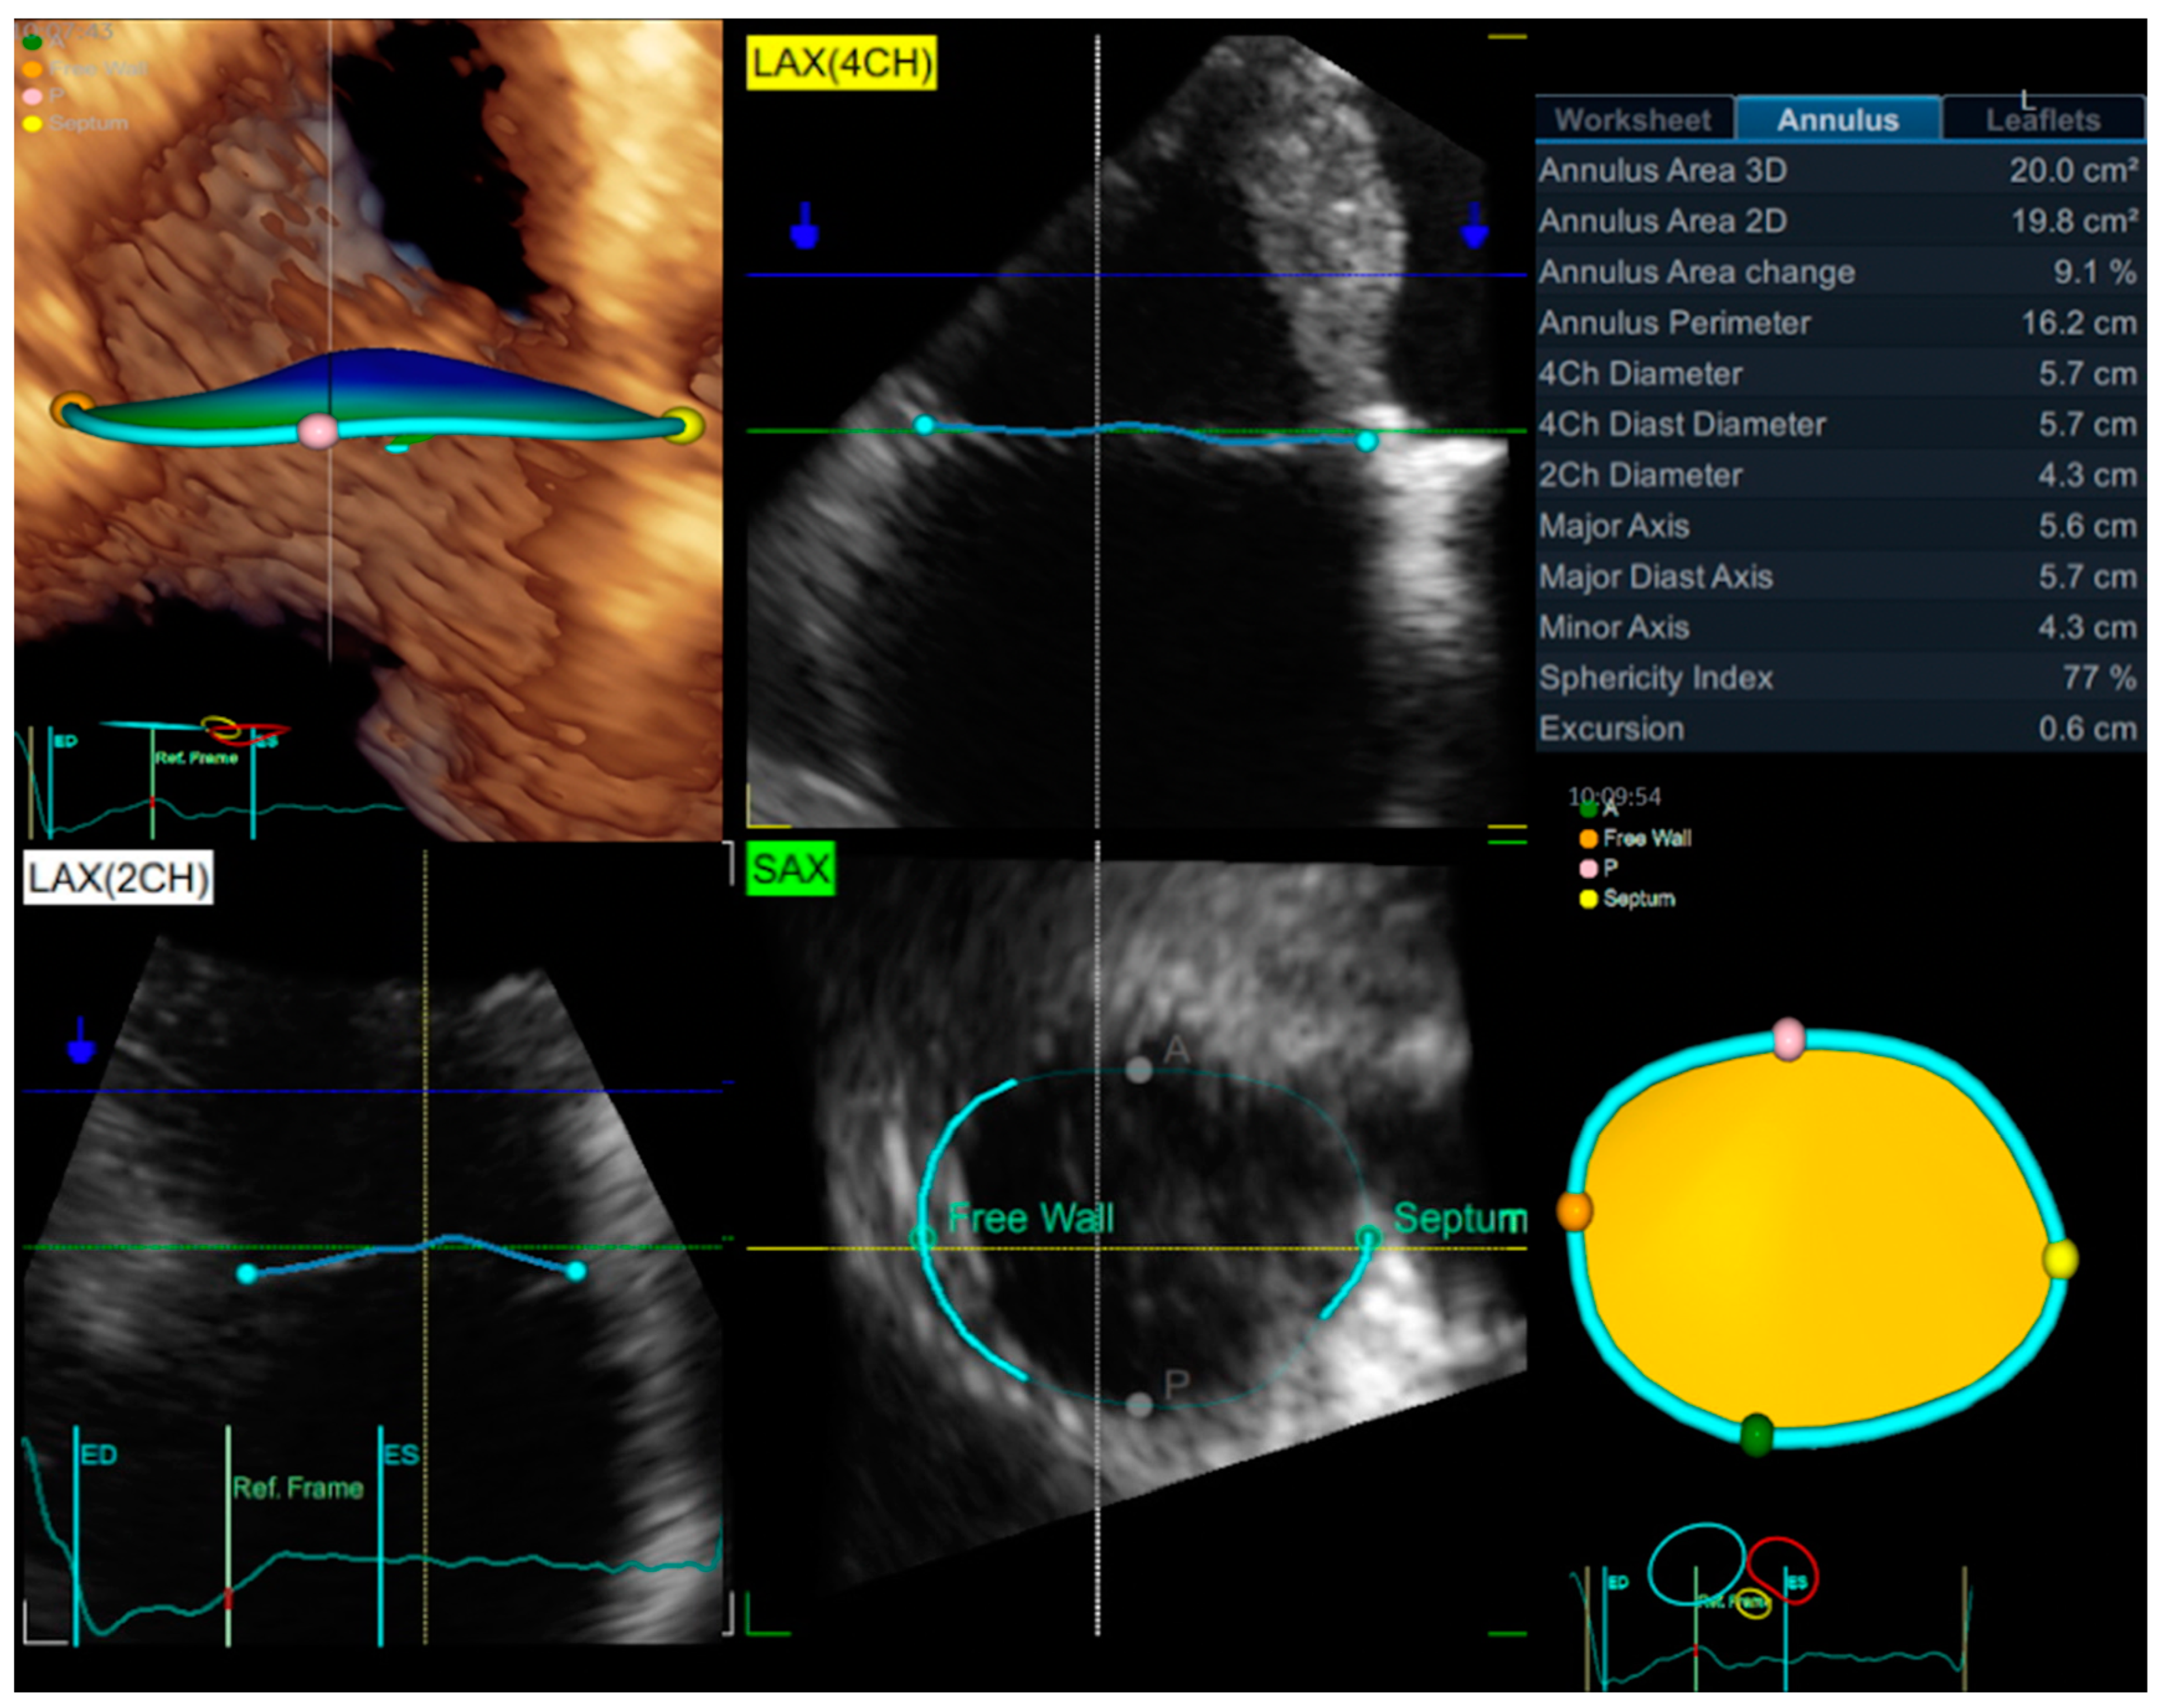

3.1. Echocardiography